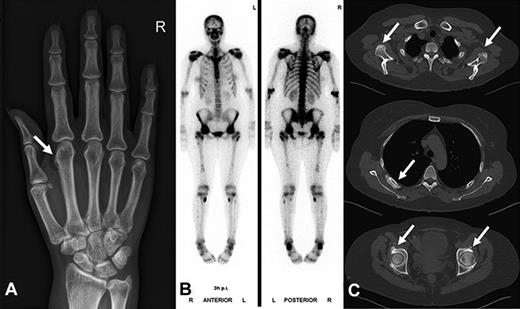

Correlation between the glomerular filtration rate, as calculated by the CKD-EPI formula, and the serum fluoride levels for the patients taking voriconazole. Spearman rank correlation coefficient = 0.74; P < .001.

The main patient characteristics of overall 32 patients with hematologic malignancies taking voriconazole (n = 20), posaconazole (n = 8), and itraconazole (n = 4), as well as a hematologic patient control group (n = 11) not receiving antifungal therapy are shown in Table 2 and in more detail in Supplemental Tables 1 and 2 (available on the Blood Web site; see the Supplemental Materials link at the top of the online article). The 3 patients with proven voriconazole-induced skeletal disease were not included in this analysis. Serum fluoride levels were significantly elevated in patients receiving voriconazole (median, 157 μg/L; IQR, 97 μg/L) compared with itraconazole (median, < 30 μg/L; IQR, 28 μg/L), posaconazole (median, < 30 μg/L; IQR, 0 μg/L), and the control group without antifungal medication (median, < 30 μg/L; IQR, 28 μg/L; P < .001 for all comparisons; Figure 3). The fluoride level in the voriconazole treatment group was inversely correlated to the glomerular filtration rate (Spearman rank correlation coefficient = 0.74; P < .001; Figure 4). Radiologically typical skeletal disease (periosteal appositions, abnormal calcifications) was seen in the CT scan of 1 asymptomatic patient (5%) in the voriconazole group and none in the other treatment groups. Disseminated bone pain consistent with skeletal disease was present in 3 (15%) patients in the voriconazole group and none in the other treatment groups. No signs of skeletal disease were detected in 2 of these patients by chest CT scan, whereas the third patient had no radiologic examinations performed during the observation phase. Additional fluorinated drugs were given in only 1 patient (posaconazole group), and no increase in serum fluoride level was noted.

But why do only some patients on voriconazole treatment develop clinically relevant skeletal disease? (1) Fluoride is mainly excreted by the kidneys, and an impaired renal function leads to higher circulating fluoride levels.18,19 Indeed, the fluoride level in our voriconazole treatment group was inversely correlated to the glomerular filtration rate, and all our patients with proven voriconazole-induced skeletal disease had moderate to severe chronic renal failure. However, chronic renal failure alone does not necessarily translate into skeletal disease as, for example, 6 additional patients with voriconazole treatment and moderate chronic renal failure did not show evidence of toxicity. (2) It is known from endemic fluorosis that prolonged intake promotes toxicity, and it seems reasonable to assume that this also holds true for patients exposed to fluorinated drugs, even though our data lack the statistical power to test this. (3) We hypothesize that pharmacogenetics and drug-drug interactions may account in part for the interindividual differences. (4) We speculate that inflammatory processes play an additional role as the symptoms in our patients were temporarily attenuated by adding corticosteroids and methotrexate and the pain rapidly resolved after cessation of voriconazole, even though the radiographically visible skeletal changes clearly needed more time to resolve.